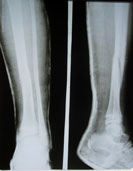

Рентген после снятия гипса и перед операцией.

Сообщение Darya »

Рентген